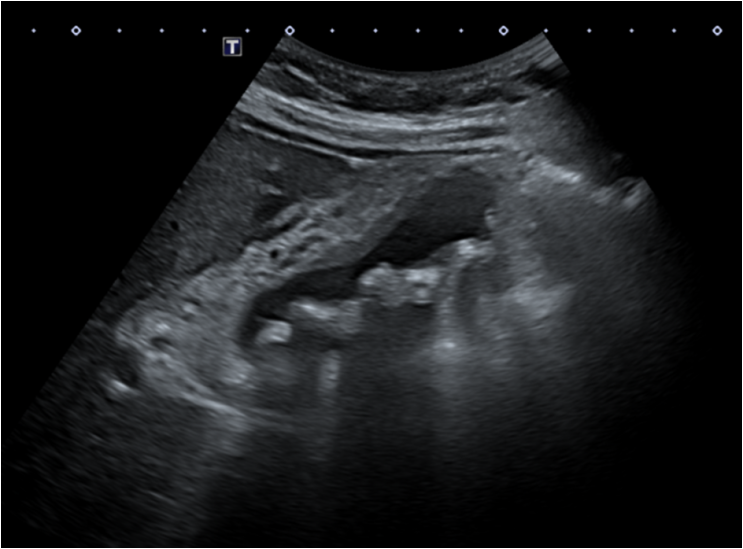

진료 후 기본 피검사, 복부초음파로 확인을 하였고, 복부 초음파상에서 담낭 주위로 지저분한 에코와 여러 개의 담낭 돌을 확인할 수 있었습니다. 이는 급성 담낭염의 전형적인 소견으로 피검사상에서도 염증수치가 많이 올라가 있었습니다. 결석성담낭염 진단, 급성 담낭염은 수술적인 치료까지 필요한 상황이라 상급병원으로 전원을 하였습니다.

• 복부초음파: 담낭 주위 지저분한 에코와 담낭 돌 복부초음파: 담낭 주위 지저분한 에코와 담낭 돌